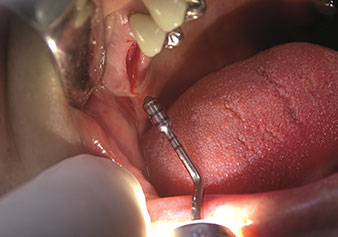

Eine oft unterschätzte Anwendung ist die schonende Extraktion von Zahnwurzeln oder auch von Wurzelfragmenten im Rahmen des Alveolenmanagements. Mit den feinen Periotomen, die aktuell in zwei Ausführungen (EX1 und EX2 von W&H) zur Verfügung stehen, lassen sich auch speziell endodontologisch vorbehandelte Zähne oder ankylosierte Wurzeln mühelos entfernen. Das Ergebnis sind Extraktionsalveolen, deren Hart- und Weichgewebe völlig intakt sind, da in der Regel auf ein Aufklappen verzichtet werden kann.

Dies stellt anschließend eine optimale Basis für eine spätere oder Sofortversorgung mit Implantaten dar (Abbildung eins und zwei mit freundlicher Genehmigung von Dr. Torsten Conrad, Bingen a. Rhein).

Foto: © Dr Torsten Conrad (Bingen a. Rhein)